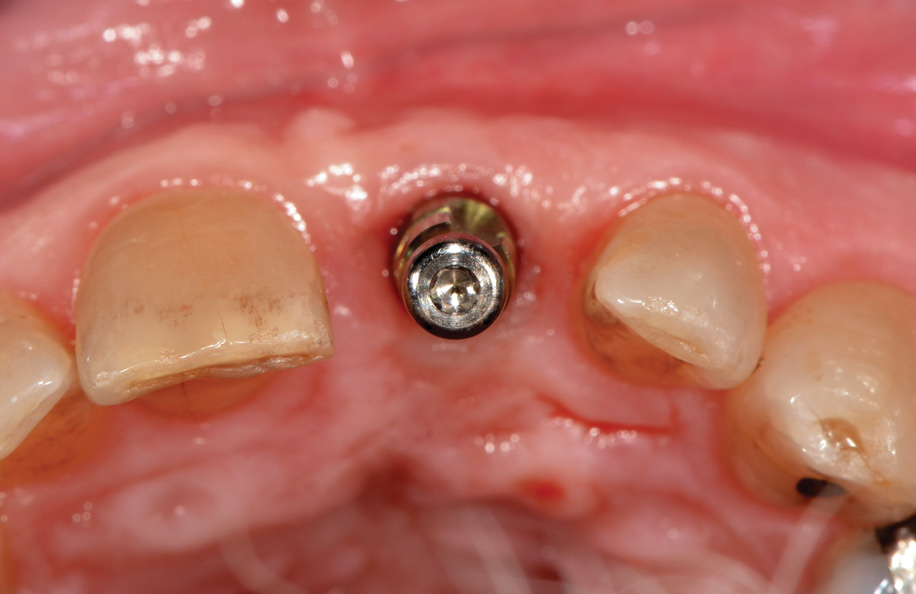

Fig 1. Incisal view (clinical) with impression coping in place demonstrating buccal angulation of implant.

Figure 1